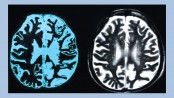

In stroke, there is damage to the brain tissue either due to cerebral infarction or hamorrhage. World Stroke Day is October 29. It is observed to bring global attention to urgent need of taking action…